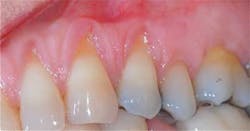

Postop: Eight-month reevaluation